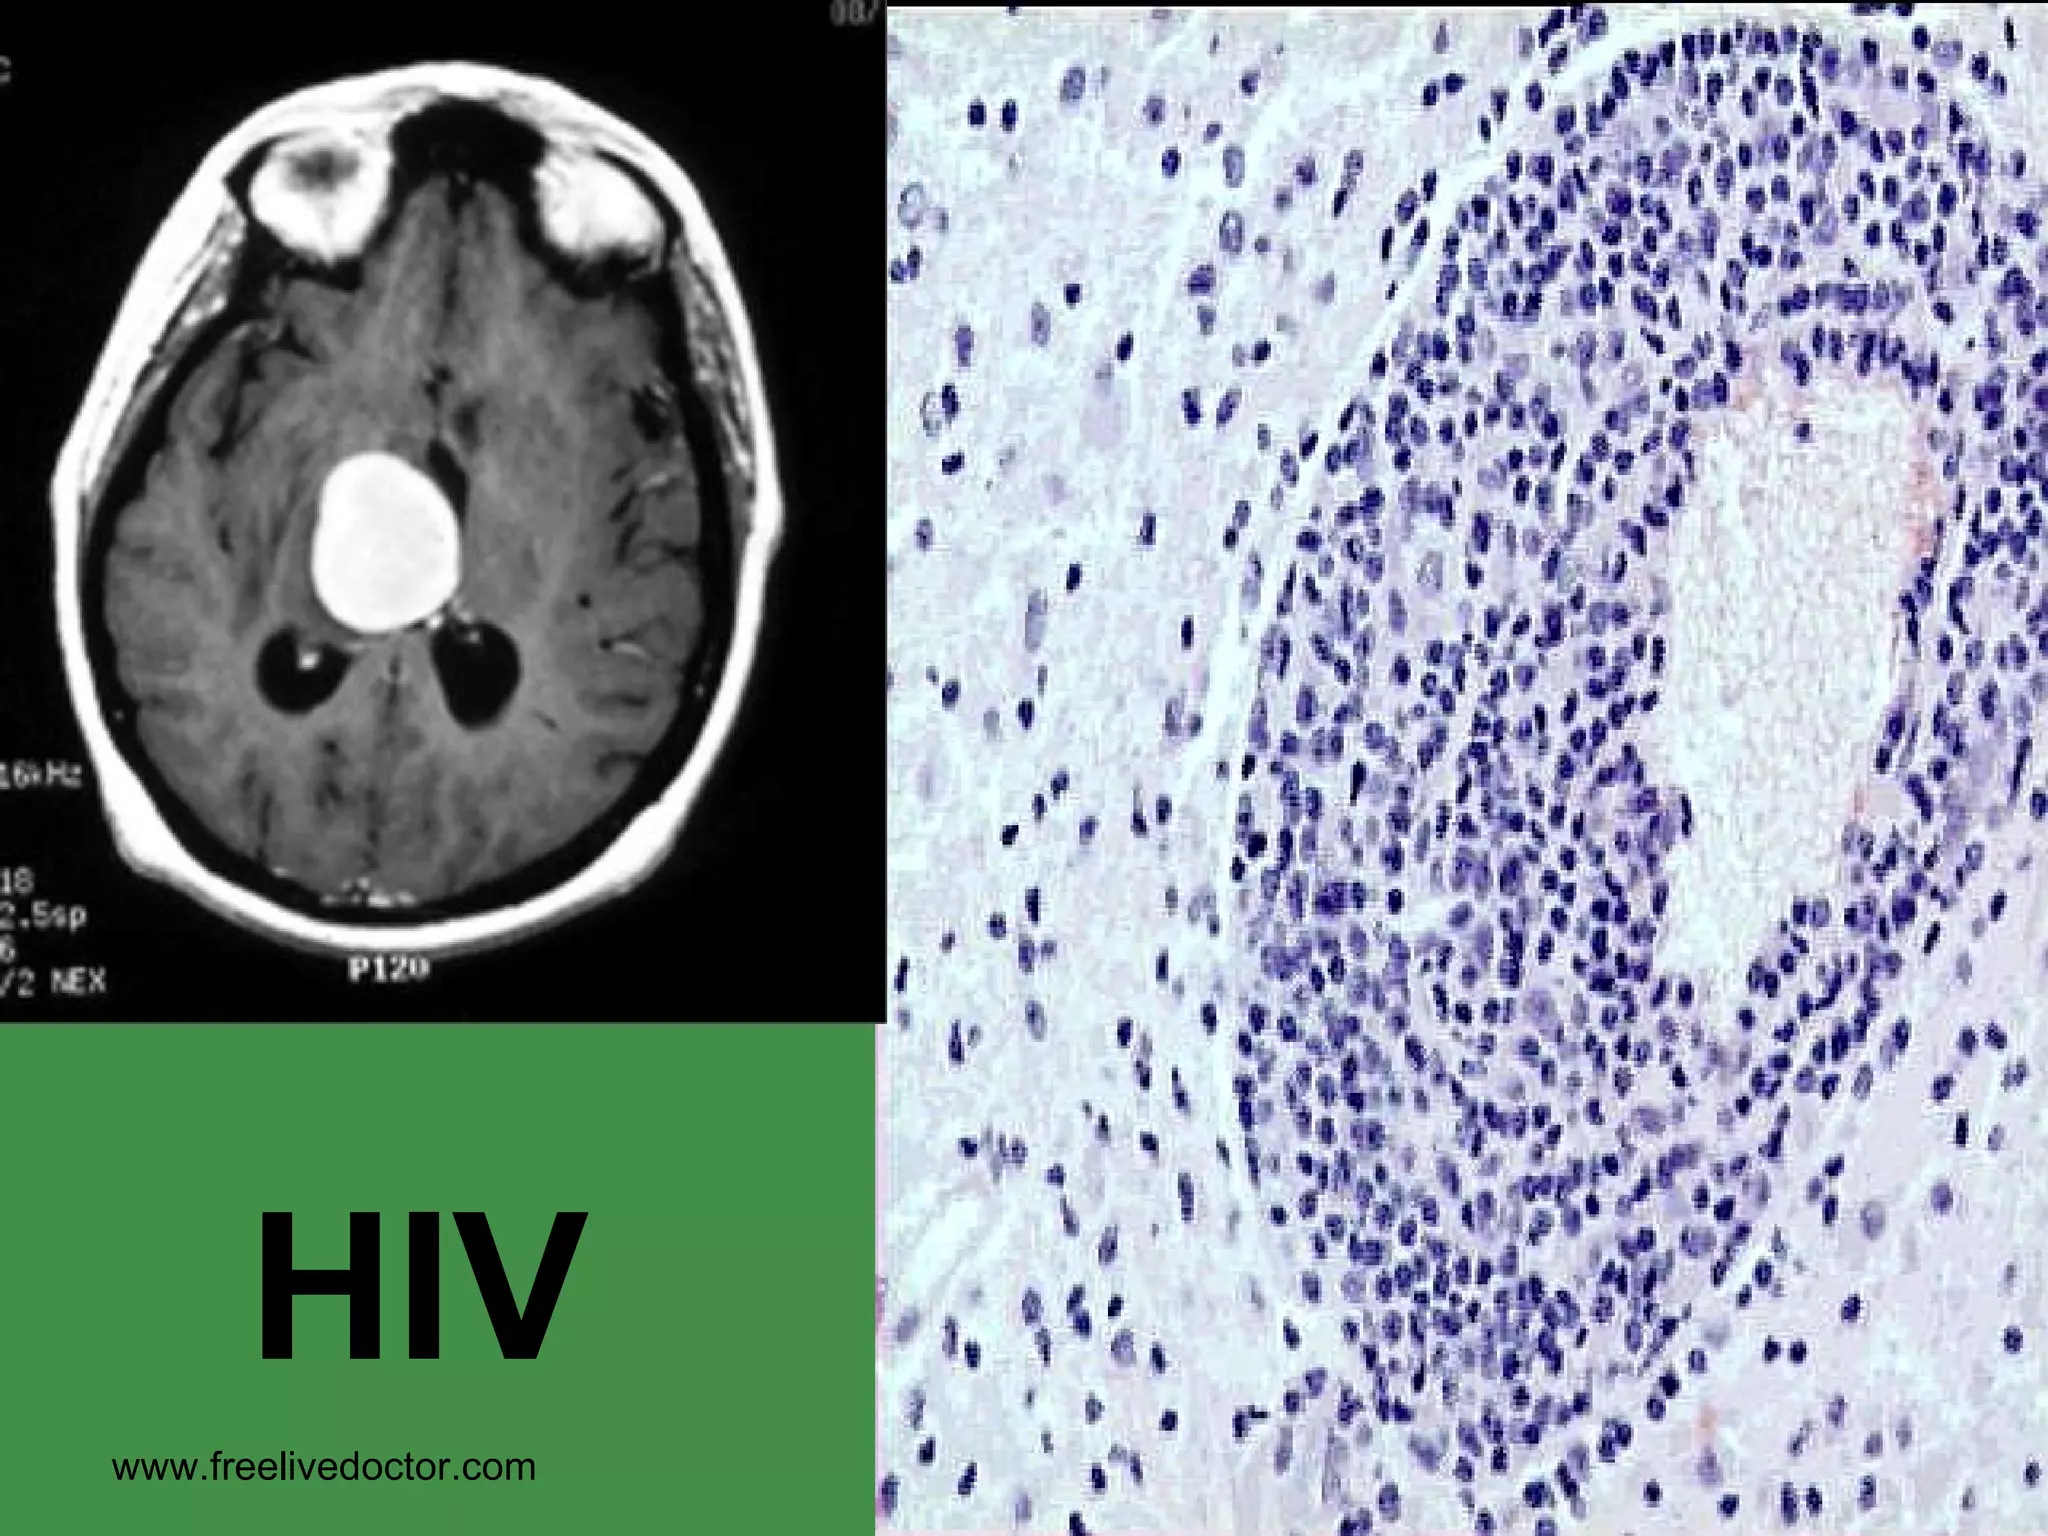

VIRAL ENCEPHALITIS PERIVASCULAR LYMPHOCYTIC “ CUFFING” www.freelivedoctor.com

PERIVASCULAR GIANT CELLS in  WHITE MATTER in HIV ENCEPHALITIS www.freelivedoctor.com

HIV www.freelivedoctor.com